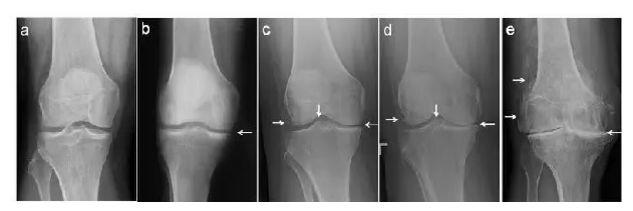

截骨矫形 部分患者可能由于下肢骨发育畸形,膝内翻或膝外翻畸形等原因导致下肢力线偏移,膝关节单侧受累,但是活动度基本正常,此时患者年龄多较小,但膝关节常存在持续性疼痛,这种情况常采用胫骨高位或股骨髁上截骨术,尽量保留膝关节,延缓膝关节退变的速度。

关节置换 针对退行性关节炎晚期,由于软骨剥脱,关节间隙变窄,关节重度退变,患者常存在持续性疼痛,甚至无法行走,此时就需要将退变磨损的关节面换掉。针对膝关节单侧受累的情况,可以选择单髁置换术,针对终末期膝关节骨关节炎全关节均已退变的患者,则需要人工全膝关节表面置换术,将膝关节完全更换为人工假体。